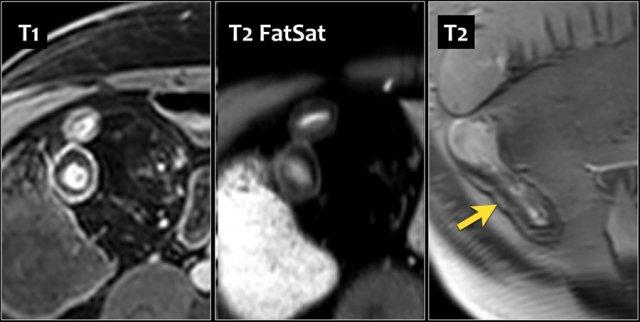

Dày thành hồi tràng cuối ở nam giới 67 tuổi mắc bệnh Crohn 11 năm. Ngấm thuốc phân lớp được thấy trên hình ảnh T1 axial sau tiêm thuốc tương phản từ có fat-sat (trái). T2 có fat-sat (giữa) cho thấy cùng kiểu với lớp giữa giảm tín hiệu. T2 không có fat-sat cho thấy tăng tín hiệu ở lớp giữa, gợi ý lắng đọng mỡ. Nội soi chỉ phát hiện tổn thương nông.